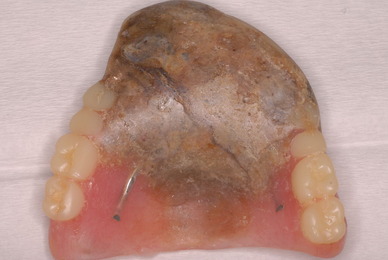

カビか何かが入り込んでいる異様な入れ歯でした。